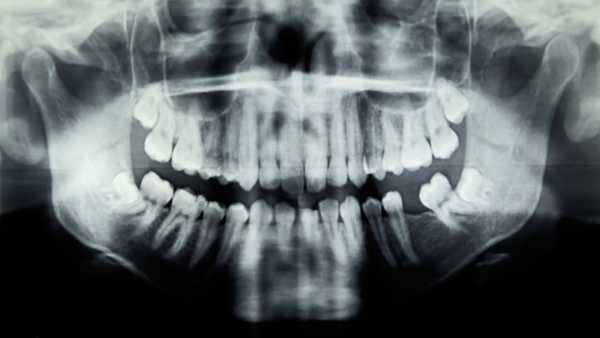

Діагноз: Ендоскопія виявила велике утворення в шлунку жінки, відоме як шлунковий безоар. Ці маси являють собою щільно упаковані грудки частково перетравлених або неперетравлених матеріалів.

Що робить цей випадок унікальним: у звіті зазначається, що безоар шлунка зустрічається досить рідко. Він виявляється менш ніж у 0,5% ендоскопій верхніх відділів травного тракту. Поширені симптоми цього стану, такі як біль, нудота, блювота та дискомфорт у животі, також з'являються при багатьох поширеніших захворюваннях, тому вони не обов'язково вказують на наявність безоару у всіх випадках.

Найпоширеніший тип шлункового безоару утворюється з рослинних волокон і називається «фітобезоаром». Вживання великої кількості певних продуктів, таких як хурма, ананаси, родзинки або селера, може підвищити ризик розвитку фітобезоару, оскільки рослини містять високу концентрацію неперетравлюваних компонентів, таких як целюлоза, лігніни та деякі таніни.